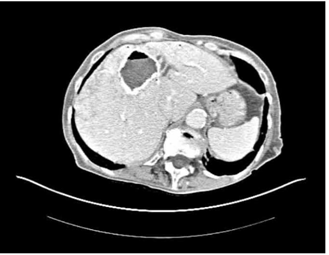

- בטומוגרפיה ממוחשבת ניתן לראות גוש בכבד עם כיסיות בנות, עם מחיצות או בלעדיהן (תצלום 12.10 - 13.10)